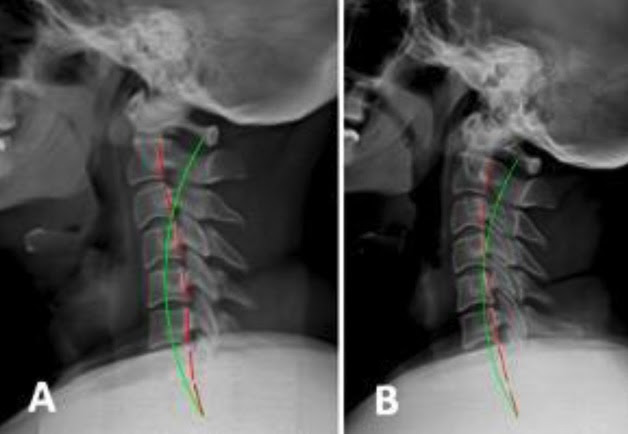

“Long-term stability of reducing cervical kyphosis via Chiropractic Biophysics® extension traction procedures: a case series”

Authored by Tim C. Norton, DC, Paul A. Oakley, DC, Jason W. Haas, DC, and Deed E. Harrison, DC, this newly published case series examines five patients with cervical kyphosis treated using CBP® rehabilitation protocols.

- 24° average increase in global cervical lordosis

- 18° reduction in regional cervical kyphosis

- Over one-year follow-up, only a 10° regression in lordosis with no loss of disability improvement